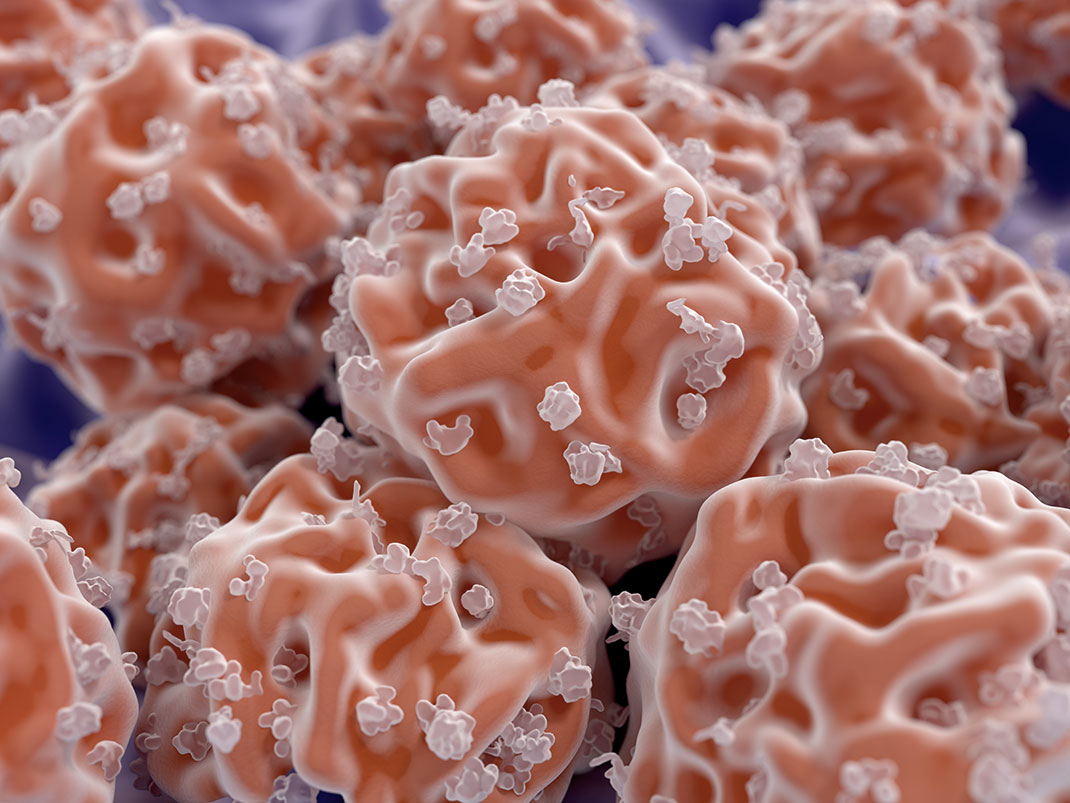

Un accident vasculaire cérébral (AVC) est un déficit neurologique soudain d’origine vasculaire causé par une hémorragie ou par un vaisseau sanguin bouché, entraînant l’interruption de la circulation du sang vers le cerveau. En France, ils frappent près de 150 000 personnes par an. Les AVC sont la première cause de handicap dans le monde entier. De nombreux centres de recherche tentent de trouver un moyen de soigner les patients atteints de séquelles, notamment à l’aide de cellules souches mésenchymateuses extraites de la moelle osseuse et du tissu adipeux de donneurs.

L’équipe de chercheurs a donc injecté des cellules mésenchymateuses modifiées génétiquement directement dans la zone touchée du cerveau des patients. Aucun problème de tolérance notable n’a été relevé suite à cela, bien au contraire les scientifiques sont parvenus à une conclusion très encourageante : ils ont observé une certaine amélioration de l’état des patients suite à l’injection. « Ce n’était pas simplement qu’ils ne pouvaient pas bouger leur pouce et qu’ils en deviennent capables. Des patients qui étaient en fauteuil roulant remarchent », s’extasie Gary Steinberg.

Mais les chercheurs se sont rendu compte que ce progrès soudain n’est pas uniquement dû à l’injection des cellules souches car celles-ci ont totalement disparu au bout d’un mois. Ils sont donc parvenus à la conclusion que les cellules transplantées agissent en aidant le cerveau à se réparer puis à cicatriser grâce à la sécrétion de plusieurs substances. Jusqu’à cette découverte encourageante, les médecins n’avaient pas de véritable solution à proposer à leurs patients car six mois après un AVC les lésions neurologiques sont difficiles à renverser. Ainsi cette méthode donne un véritable espoir à toutes les personnes atteintes de séquelles.